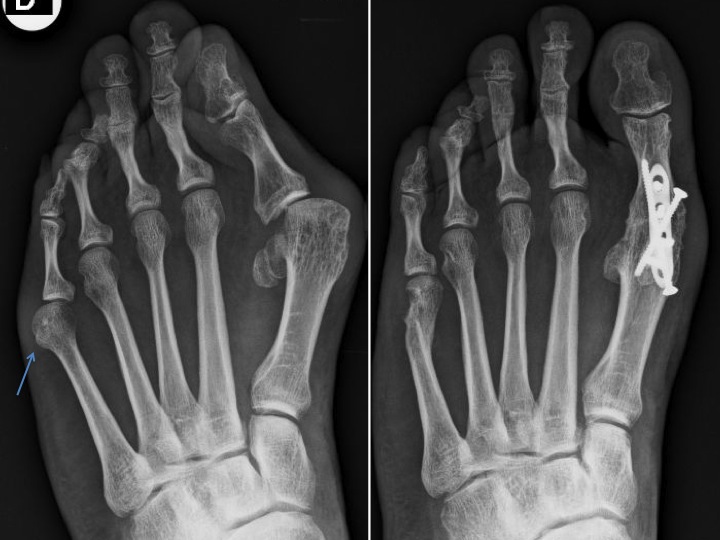

Si le traitement conservateur, basé sur des chaussures adaptées et des soins podologiques, ne suffit plus, on peut proposer une opération. C’est par une ostéotomie (ouverte ou percutanée) qu’on corrigera la déformation, dépendante du type de bunionette et analysée par une radiographie du pied en charge.

Type 2 : dans 23% des cas : courbure latérale excessive du cinquième métatarsien ; une ostéotomie distale peut réajuster cette déformation.